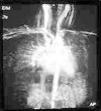

Niño de 8 años que consultó por crisis de broncoespasmo desde la edad de 8 meses y asoció cuadros de neumonías de repetición a los 16 y 33 meses con afectación del segmento posterobasal del lóbulo inferior izquierdo y ocupación del seno costodiafragmático izquierdo, requiriendo ingreso hospitalario. El tercer episodio, con los mismos hallazgos fue tratado de forma ambulatoria a la edad de 6 años. La prueba de tuberculina fue negativa en todos los casos. Antecedentes familiares: sin interés. Antecedentes personales: gestación, 39 semanas. Ecografías prenatales normales. Amniocentesis: normal. Cariotipo: 46XY. Parto: cesárea por desproporción pelvi-fetal. No patología del líquido amniótico. Período neonatal normal. La exploración clínica mostró hipoventilación basal izquierda con crepitantes localizados. Las exploraciones complementarias practicadas fueron: hemograma normal. IgE: 7 UI/ml. IgG, A y M, C3 y C4 normales. Alfa-1-antitripsina: 118 mg/dl. Cloruros en sudor: negativo. Prick estándar de neumoalérgenos negativo. Electrocardiograma y ecocardiografía: normal. Espirometría basal: patrón ventilatorio mixto (obstructivo-restrictivo) leve con test de broncodilatación positivo (ΔFEV1: 18 %). Radiografía de tórax en inspiración y espiración (fig. 1): disminución de volumen de pulmón izquierdo con arteria pulmonar izquierda de menor tamaño y desplazamiento mediastínico ipsolateral, sin evidencia de atrapamiento aéreo, con aumento de tamaño de la arteria pulmonar derecha. Tomografía computarizada (TC) torácica sin contraste (fig. 2): disminución de volumen pulmonar izquierdo con arteria pulmonar izquierda pequeña y vena pulmonar inferior izquierda pequeña, así como aumento de la vascularización pulmonar derecha. La angiografía por resonancia (angio-RM) (fig. 3) confirmó la existencia de arteria pulmonar izquierda pequeña, con disminución de la vascularización de dicho pulmón y venas pulmonares de pequeño tamaño. Se observó un aumento de la arteria pulmonar derecha y de la vascularización de pulmón derecho, sin observar alteraciones cardíacas ni de grandes vasos asociadas. Estos hallazgos nos permitieron establecer el diagnóstico de hipoplasia pulmonar.

Figura 3. Angio-RM que muestra la ausencia de alteraciones cardíacas y de grandes vasos.